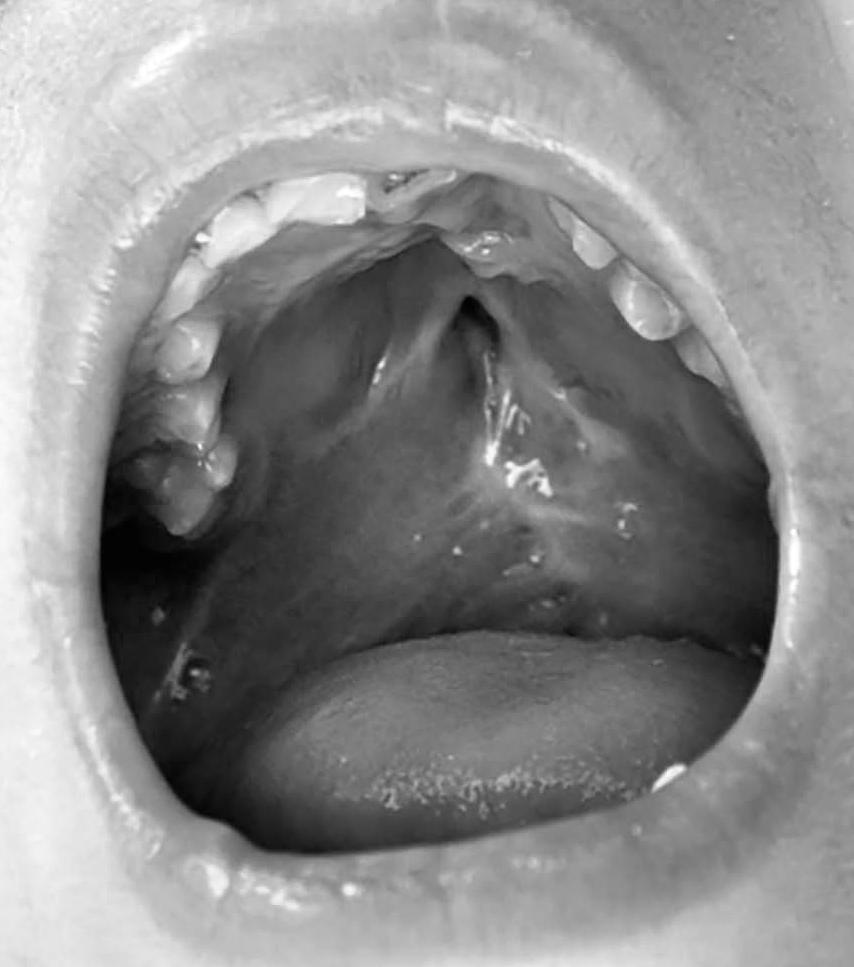

Aquí tienes una descripción detallada de cómo se visualizan los diferentes tipos de fisuras y hendiduras en casos de labio y paladar hendido. En el ámbito médico, estas imágenes se clasifican según qué estructuras están afectadas (labio, encía, paladar duro, paladar blando) y cuánto se extienden.